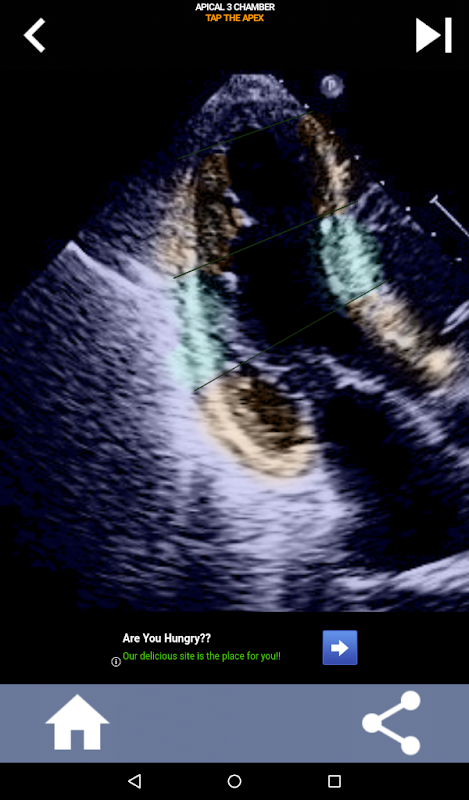

এই অ্যাপটি প্রকৃত ইকো ইমেজ ব্যবহার করে আপনার জ্ঞান পরীক্ষা করবে, যা আমি প্রায়শই সেরা শিক্ষার পদ্ধতি বলে মনে করি।